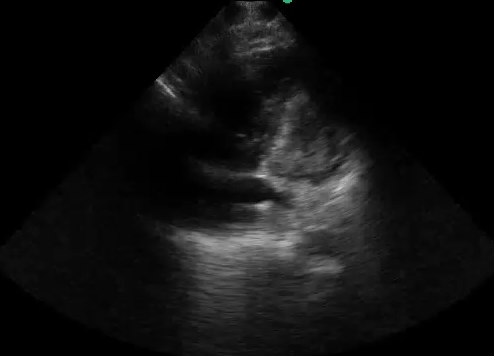

Image Acquisition: Basic Focused Assessed Transthroacic ECHO (FATE) was performed (See videos below).

Image Interpretation: Pericardial effusion was absent yet the right ventricle (RV) was dilated acutely as the RV wall thickness was normal (subcostal).  The systolic D-septum (parasternal) suggested an elevated RV afterload.  Along with the hyperdynamic left ventricle (LV) and normal left atrium (LA), there was likely a flow obstruction between the RV to LA which maybe related to the “lesion” in the RV.

The four basic cardiac views were attained though the quality varies with the apical 4 view being the least favourable with the patient in an upright position and taking rapid breaths. In practice, especially during acute situations, positioning for the ideal windows may not be feasible; and, often, not all windows can be obtained.

The first and foremost PoCUS interpretation parameter to answer is whether quality of the acquired images is adequate: pristine to unreadable. The images attained were not ideal: the septum of the parasternal long view was not horizontal; the apical 4 view was off axis; and etc… Nevertheless, they sufficed to answer the author’s clinical questions (indications).